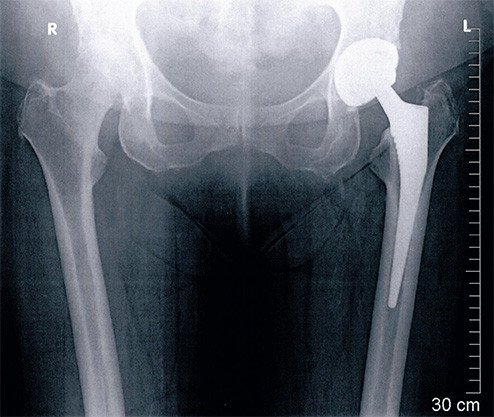

Beim Wiedereinbau wurde bei der Patientin erneut ein zementfreier Schaft eingesetzt. Die Pfanne, welche meistens ein luxationssicheres Modell ist, wurde hier mit Knochenzement im Beckenknochen fixiert. Bei der Revisions-Operation zeigte sich, dass der Muskel wieder vollständig angewachsen war. Die Hüfte ist dann sofort voll belastbar. Zwei Monate später ist die Patientin mit dem Verlauf zufrieden, sie ist gut gehfähig, es ist kein Hinken mehr vorhanden.